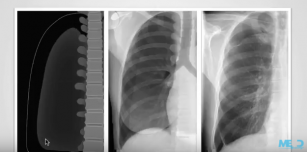

How to identify pneumothorax on a chest X-ray. 6th Mar 2018 - Julian Dobranowski, MD, FRCPC Identify when pleura is abnormal and the key radiological signs of pneumothorax.